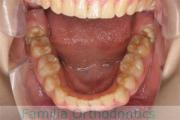

No.14V-516

- 上顎前突

- 叢生

- 10歳

- 女性

- 上:

- 44

- 下:

- 55

- 主な使用装置:

- FEA

- 治療にかかった費用:

- 90万円

きれいな歯並びにしたいということで来院されました。第一期治療で六歳臼歯の位置を維持する装置を入れて第二期治療の準備をしました。第二期は中学生になってから小臼歯を抜歯して行いました。二期治療は約2年半、25回程度の通院が必要でした。

- ≫治療後

二期治療開始前は叢生(でこぼこ、凹凸、ガタガタ)がかなりありましたので、保定をしっかりしないと段差ができてきたり後戻りのリスクがあります。